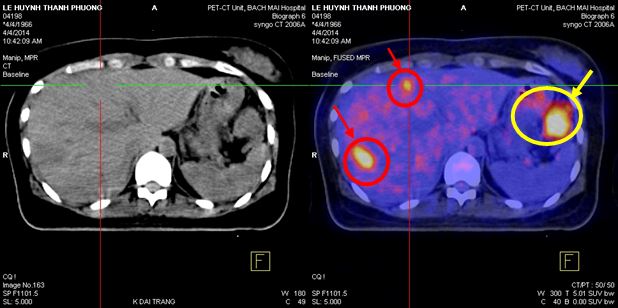

Chụp PET/CT :

- Trong nhu mô gan có nhiều khối tăng hấp thu F-18 FDG, khối lớn nhất hạ phân thùy VII, max SUV=9,1 (kích thước 3,3x4,7x3,6cm), các khối khác, max SUV=4,59 (kích thước 2,7x3,5x3,0cm), max SUV=3,2 (kích thước 2,6x2,9x2,8cm)

- Đại tràng góc lách có khối kích thước 5,2x6,8x6,7cm, làm hẹp lòng đại tràng, tăng hấp thu F-18 FDG, max SUV=12,1

Hình 1,2,3: Hình ảnh chụp PET/CT toàn thân: Vòng tròn đỏ là tổn thương tăng hấp thu F-18 FDG tại u gan và vòng tròn vàng là hình ảnh khối u đại tràng góc lách